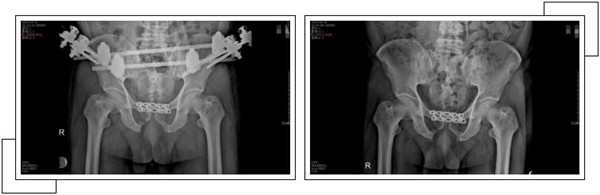

二周后,赵大叔病情稳定,身体各方面条件符合手术指征后,骨科中心副主任罗军带领手术团队为其进行了骨盆骨折、耻骨联合分离、双侧髂骨骨折、右侧耻骨上下支骨折切开复位内外固定术,手术一个半小时顺利完成。

经过关节科全体医护人员的精心治疗和护理,术后一个月,赵大叔康复出院。出院当天,赵大叔感谢的话说了又说,并在来复查时,特地制作了一面锦旗以表示谢意。